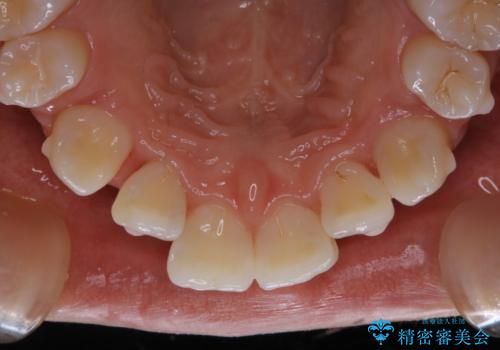

- インビザラインでのマウスピース矯正中に着色が気になるとのことでした。着色が全体的に付着していたためPMTC60分コースを行いました。

PMTC(保険外治療)は、毎日の歯磨きで落としきれない汚れや、コーヒ、紅茶・タバコのヤニなどの着色も除去します。目には見えない歯と歯の間・歯肉の境目・インビザライン中はアタッチメント周囲などに残っているプラーク(歯垢)もしっかり取り除きます。PMTCでは専門的な機械や材料を使用して、徹底的に汚れを除去するため、虫歯・歯周病・口臭予防などにつながります。

またPMTCを行うことで、ご自身本来の歯の色になり自然な明るさになります。